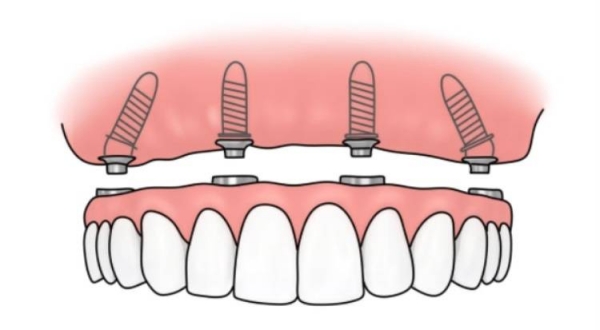

C. 设计细节:微螺纹与锥形连接

它的设计考虑到了东方人牙槽骨相对偏窄、偏软的特点。顶部的微螺纹设计能有效分散咬合压力,防止骨吸收(也就是防止牙龈萎缩导致植体暴露),这对于延长植体寿命至关重要。

需要“即刻种牙”的急脾气:如果你希望拔完牙马上种,八维的高初期稳定性设计能大幅提高成功性。